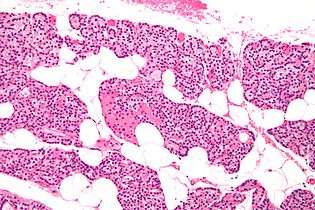

The parathyroid glands are named for their proximity to the thyroid — and serve a completely different role than the thyroid gland. The parathyroid glands are quite easily recognizable from the thyroid as they have densely packed cells, in contrast with the follicular structure of the thyroid.[7] Two unique types of cells are present in the parathyroid gland:

- Chief cells, which synthesize and release parathyroid hormone. These cells are small, and appear dark when loaded with parathyroid hormone, and clear when the hormone has been secreted, or in their resting state.[8]

- Oxyphil cells, which are lighter in appearance and increase in number with age,[8] have an unknown function.[9]

Intermediate magnification micrograph. H&E stain. The white round structures are fat cells. Adipose tissue comprises 25–40% of normal parathyroid gland tissue.[1]